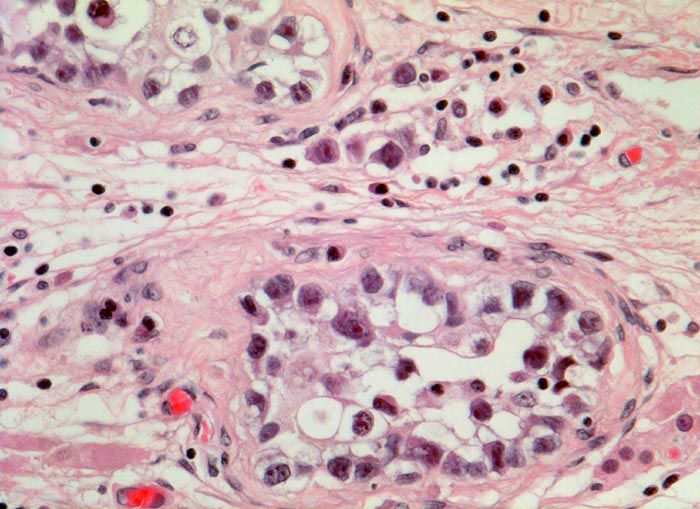

PathoPic – image database / PathoPic ID 3082 - Seminom und testikuläre intraepitheliale Neoplasie (TIN)

Seminom und testikuläre intraepitheliale Neoplasie (TIN)

maligner Tumor

Hoden

Beschreibung

Gemischter Keimzelltumor. An anderer Stelle Anteile eines unreifen Teratoms und eines Chorionkarzinoms.

St.n. Kryptorchismusoperation. Tumorknoten in einem Hoden.

Intratubuläre atypische Keimzellen finden sich nahezu bei jedem malignen Keimzelltumor des Hodens. Wenn die atypischen Zellen im tumorfreien Hoden nachweisbar sind, wird dieser in der Regel bestrahlt. Die atypischen Keimzellen enthalten viel Glykogen und sind daher PAS positiv. Ausserdem sind sie positiv für die plazentäre alkalische Phosphatase PLAP. Meist wachsen die Seminome als grössere Knoten infiltrierend. Daneben kann man auch wie im vorliegenden Fall mikroskopisch kleine Gruppen von Seminomzellen im Interstitium finden, welche über den ganzen Hoden verteilt sein können.

Histologie

320

37

männlich